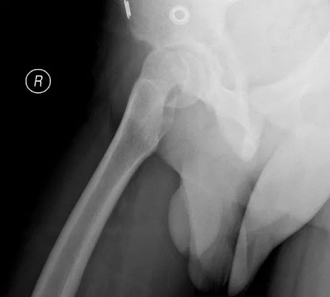

病例1 男,13岁,左侧重度SCFE

病例1 髋关节外科脱位,改良Dunn截骨,术后2年,X线示位置良好,无股骨头缺血坏死